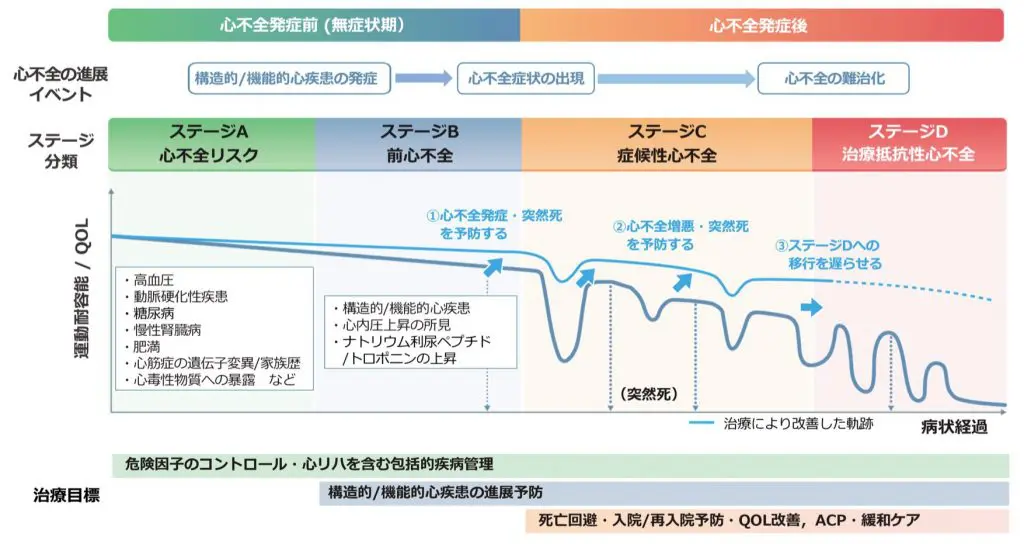

心不全のステージ分類

心不全にはステージAからDの4つのステージがあります。心不全は寛解、増悪を繰り返しながらステージが進展していきますが、このステージは基本的に一方通行で進行し後戻りができません。そのためステージの進展を抑制することが大切です。また心不全は、再入院を契機に悪化していきます(図2)。

<図2 心不全のステージの治療目標と病みの軌跡>

出典:日本循環器学会 2025年改訂版心不全診療ガイドライン